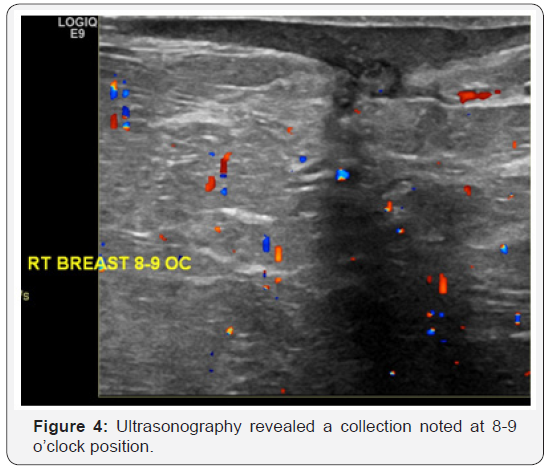

33 year-old female presented herself with pain right breast and history of TB. On clinical examination, the patient had two masses in right breast. The patient was initially examined with mammography which showed asymmetric density at right lower inner quadrant. No pleomorphic microcalcification, architectural distortion or obvious masses (Figure 1 & 2). The routine complementary breast ultrasound was done with a high frequency (8-10MHz) linear array head, which showed two collections noted at 5 and 8-9 o’clock positions (Figure 3 & 4). Finally US-guided fine needle aspiration was done. Also pathological, bacteriological analysis, and polymerase chain reaction (PCR) were done to prove the tuberculous nature of their lesions.

In our case ultrasonography finding are multiple collections and this agree with Adeiza et al. [6] stated that say lesions due to TB have no specific ultrasonographic findings. They may be heterogeneous, hypoechoic, irregularly bordered mass with internal echoes or thickwalled cystic lesions on ultrasonography. In some cases, there may be fistula formation and thickening of Cooper’s ligaments and subcutaneous tissues [6]. MRI may be used in select cases when the sonographic or CT findings are inconclusive. CT may be skipped and an MRI study may be directly performed, especially if the breast abnormality is first detected on ultrasound, to save the patient from radiation exposure. MRI is more successful for delineating the internal structure of breast TB lesions, and the central liquefaction or abscess might be easier to detect, which may potentially affect the decision for treatment approach [5].